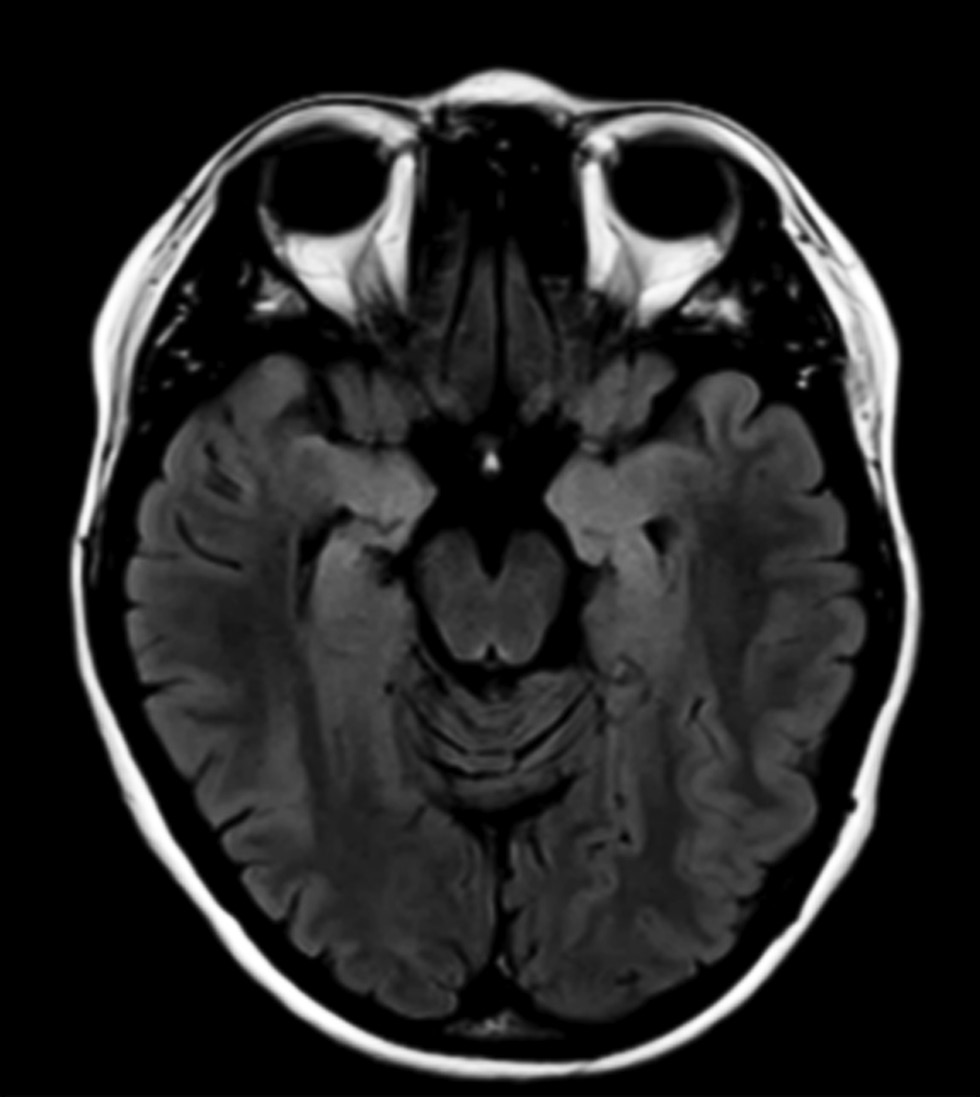

Общими чертами, характерными для большинства пациентов с GAD-ЛЭ/Э, были высокая частота приступов и/ или эпилептический статус в дебюте заболевания, клиническая картина приступов, характерная для фокальной височной эпилепсии, фармакорезистентное течение эпилепсии, наличие в структуре заболевания помимо эпилептических приступов иной очаговой неврологической симптоматики, имеющей прогрессирующий характер. У 3 (50%) пациентов отмечались умеренные когнитивные нарушения (MoCA — от 21 до 23 баллов, преимущественно за счет нарушения краткосрочной памяти, исполнительных функций). Острой психотической симптоматики не было ни у одного из пациентов, но у большинства имели место легкие поведенческие нарушения, расстройства настроения. Изменения на МРТ головного мозга были обнаружены только у 2 пациентов: у пациентки #31 — Т2-гиперинтенсивные изменения в медиобазальных отделах височных долей и атрофия обоих гиппокампов (рис. 4); у пациентки #32 — атрофия обоих гиппокампов.

Рис. 4. МРТ головного мозга пациентки #31: Т2-FLAIR, аксиальный срез — гиперинтенсивность от медиобазальных отделов височных долей (S > D), признаки атрофии гиппокампов (D > S)